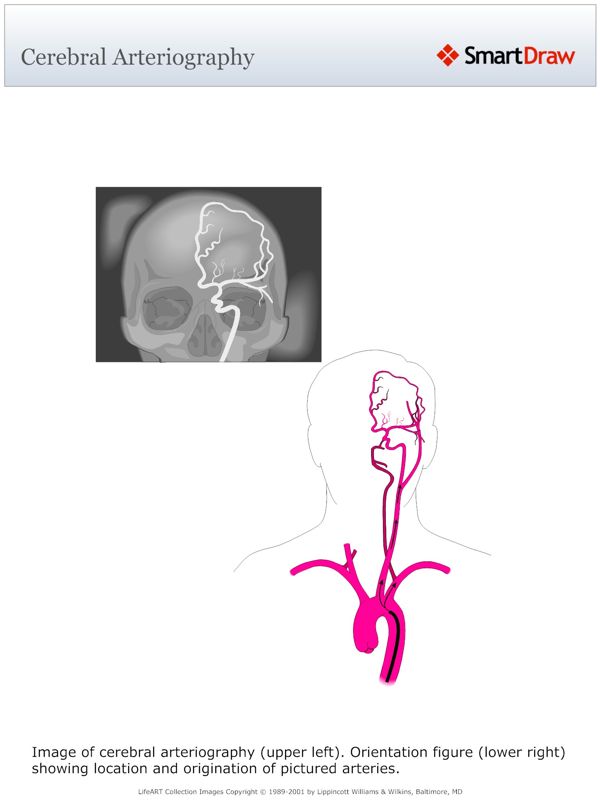

Cerebral_Arteriography